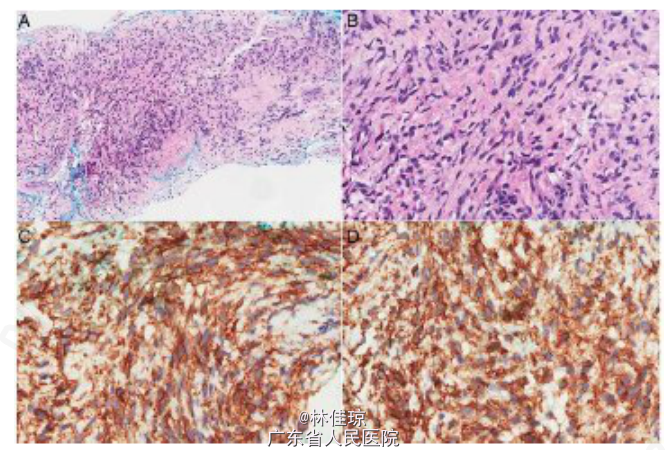

查体:生命体征正常,甲状腺肿大,中等大小,质地柔软,胸壁和右臂静脉扩张,无杵状指或发绀。第三肋下肺叩诊呈浊音,右胸下半部分呼吸音减弱;气管无偏斜。心腹查体均未见明显异常。 辅查: 末梢血血糖值为 1.9mmol/L。 血常规、生化、甲功均正常; 胸部 X 线片:显示胸部右下区占位性病变,密度均匀,界限清晰,右侧膈肌明显升高并可能膨出。 CT 扫描:胸部右下方有一巨大肿块,病变不均匀强化,大小 11.6×16.3×15.6cm;临近肋骨无破坏,但是临近肺、上下腔静脉受影响,证明为巨大胸膜纤维瘤。 组织病理学检查:对肿块进行 CT 引导下肺穿刺活检和组织学检查,可见梭形肿瘤细胞;有丝分裂像少见;梭形细胞 CD34 和 bcl-2 阳性,AE1/3 和 S-100 阴性。这些特征与孤立性纤维性肿瘤(SFT)一致。